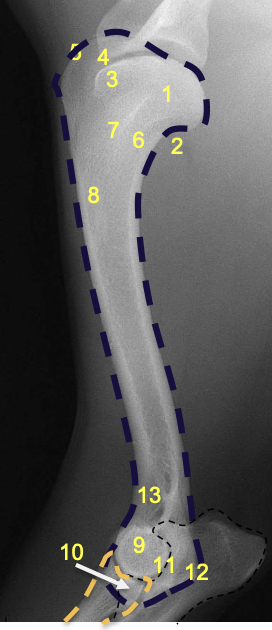

what is 8?

olecranon process of the ulna

what is 7?

olecranon of ulna

what is 1?

condyles of humerus

what is 2?

epicondyles of humerus

what is the red X marking?

anconeal process of the ulna

how does the olecranon process extend on a lateral view?

caudo-proximally

what is the relation of the medial condyle to the lateral condyle on a medio-lateral view of the elbow in a dog?

medial condyle is distal to the lateral condyle

where in the ulna is there a slight increase in opacity?

at the proximal extremity of the medullary cavity

where is the caudal ulnar cortex thicker?

in the proximal third of the diaphysis

what is the arrow at 8 pointing to?

physeal scar on distal physis of the radius